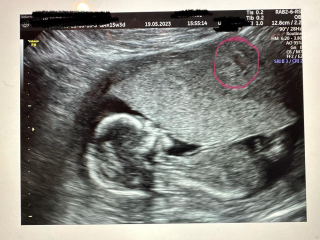

Not that it matters, I'm just wondering, do you think this but I've circled in pink is the fibroid? At 12 weeks it measured 3.5cm and if what I've circled is the fibroid it looks like it's not got bigger, which would be good. The doctor didn't mention it at all today as Prof A is looking properly next week.

@seven201 Thank you. How awful to have got all those bugs at once! Thanks for the tip, that's good to know - I've been checking my temp and it's ok. I'm glad your scan went well yesterday - such lovely photos! I don't know anything about fibroids, but what you've circled does look like it could be it - if so, glad it hasn't got any bigger and all is well x

@seven201 gorgeous pics! Sorry - I just looked and the fibroid and didn't notice the baby!! Congrats

@seven201 I'm not sure about the fibroid, but looks like it's quite far out, it's in the muscle I take it?